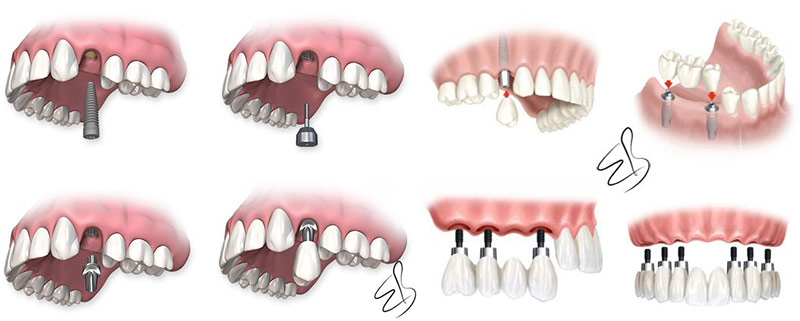

Bunlardan en uygununa karar verildikten sonra çene kemiğine implant yerleştirilir. İmplant tedavisi bir kişinin bir ya da daha fazla dişini kaybettiğinde ve yerine yeni diş yerleştirilmesini istediğinde gerçekleştirilen bir tedavi yöntemidir. Implant diş tedavisi iki aşamadan oluşmaktadır. İmplant tedavisinin süresi yapılacak olan implant sayısına ve hastanın çene kemiğine bağlı olarak yarım saat ile birkaç saat arasında da değişebilir.

İmplant diş tedavisi ne kadar sürer. İlk aşama tedavi aşaması olarak değerlendirilir ikinci aşama ise implantın kemiğe kaynama aşamasıdır. 3 3 i̇mplant tedavisi sonrasında ağız ve diş bakımı nasıl olmalıdır. Ortalama olarak 1 hafta kadar sürmektedir.

İmplant tedavisi ne kadar sürer konusu ise çene kemiğinin durumuna ve yapılan implantın uyumuna göre faklılık gösterir. İmplant operasyonunda kullanılan dikişlerin kendinden erime özelliğine sahip olması tedaviyi bir günde de gerçekleştirme imkanı sunabilmektedir. Bu aşamalarda ise yapılacak olan implant tedavisi eğer ki tek bir operasyon olacak ise bu işlem yine hastanın durumunda göre. İmplant tedavisi cerrahi bir operasyonla yapılmaktadır.

Eğer yapılacak olan tek bir implant operasyonu ise bu işlem 10 dakika ile 30 dakika arasında değişmektedir. Aynı zamanda bu işlemler cerrahi bir operasyon ile yapılmaktadır lokal anestezi ve hastanın durumuna göre genel anestezi uygulanmaktadır. İmplant tedavisinin süresi her hasta için farklılık göstermektedir.